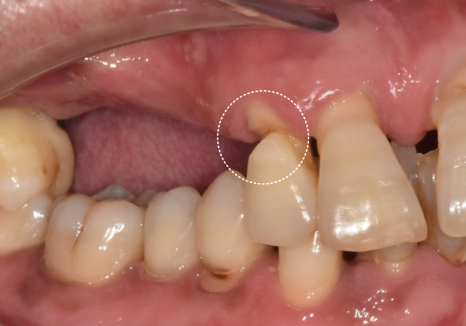

특히, 틀니 고리가 걸리는 치아들에

너무 많은 힘이 쏠리다 보니,

250531

뿌리 쪽이 심하게 패어

몹시 약해진 상태였습니다.

이렇게 되면 틀니를 아무리 새로 맞춰도

잇몸만 아프고 제대로 씹기가 참 힘듭니다.